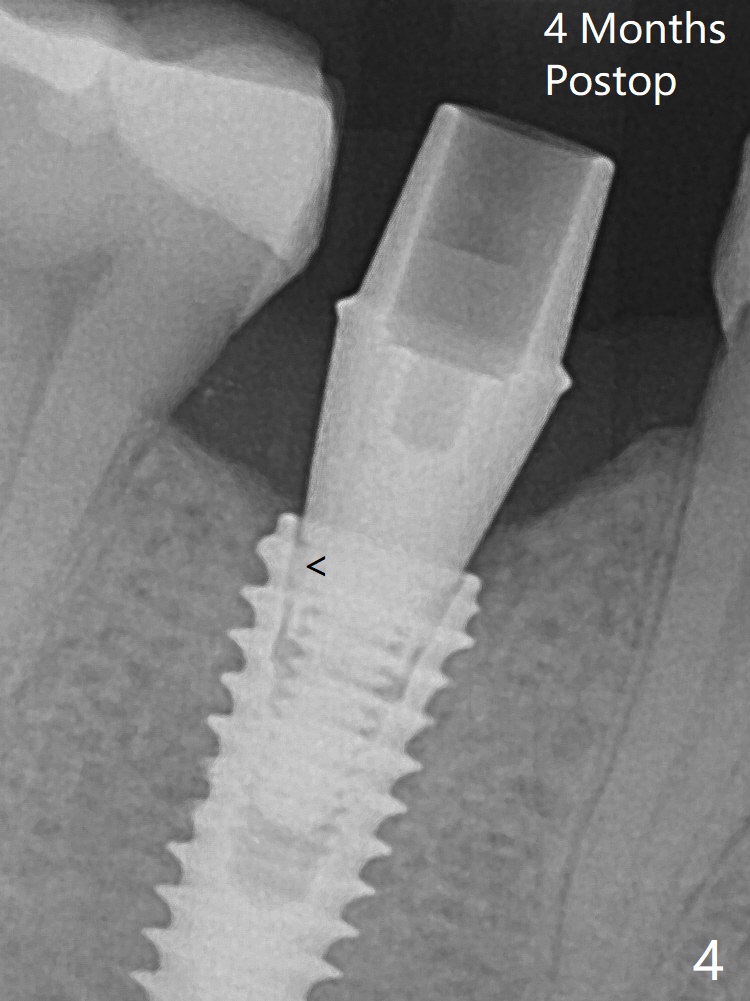

Osteotomy starts in the lingual slope of the socket of #29 with Point/Lindamann bur, but a little too distal. Gradually the osteotomy is moved mesial; the trajectory and position (Fig.1) are better than designed, but the osteotomy is close to the Mental Loop (red dashed line). When a 4x11.5 mm implant is placed, it appears to overlap the buccally positioned Loop (Fig.2 red dashed line). In fact there is no postop paresthesia. The implant placement level seems to be ideal (Fig.3 after bone graft). There is foul smell from the immediate provisional; in fact it may be due to the loose contact between the implant and abutment (Fig.4 < (4 months postop)). The gingiva is unhealthy. A 5.5x5 mm healing abutment is placed. When the patient returns 5 months postop, the gingiva is healthy after removal of the healing abutment. A 4.5x4(4) mm cemented abutment is seated without interference and torqued to 35 Ncm (Fig.5).